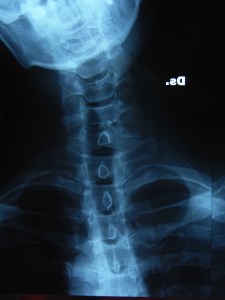

* le foto delle radiografie di Antonio in flessione laterale destra e sinistra.